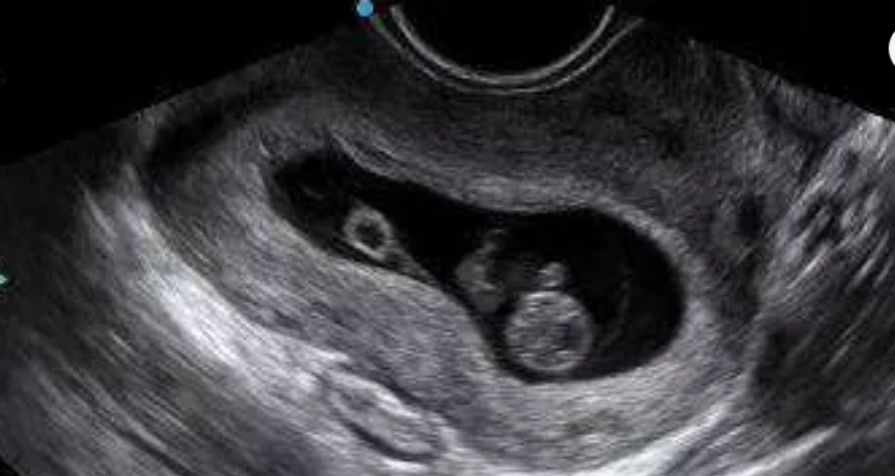

1、有几个胚胎?

2、胚胎在宫内还是宫外?

3、胚胎是否存活?

4、如果是多胎妊娠,需要确定单卵还是双卵,还要准确的判断孕周。